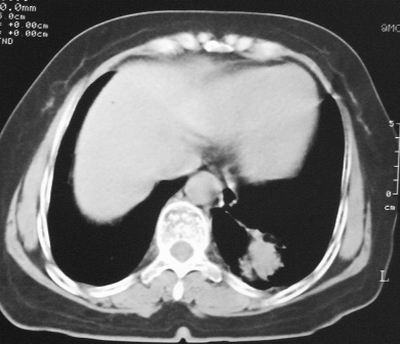

患者,女,64岁,4年前左腮腺"多形性"腺瘤手术治疗史.现复查胸部ct见左下肺块状影,该影与原左腮腺手术是否有联系?

本次复查胸部ct

我考虑炎性假瘤:1,边界模糊.2,邻近胸膜增厚,胸膜外脂肪也增厚.3,周围有肺气肿征.4,无胸水,无淋巴结肿大.

肿块周围提示慢性改变,邻近胸膜外脂肪有沉积,考虑为良性,炎性假瘤可能。

左下肺后基底段实性肿块,周围有毛刺,病变周围有肺气肿,与降主动脉间有条带状影相连,病灶4年前查体发现,纵隔内未见肿大淋巴结。考虑.肺隔离症,建议增强扫描与周围型肺癌鉴别。